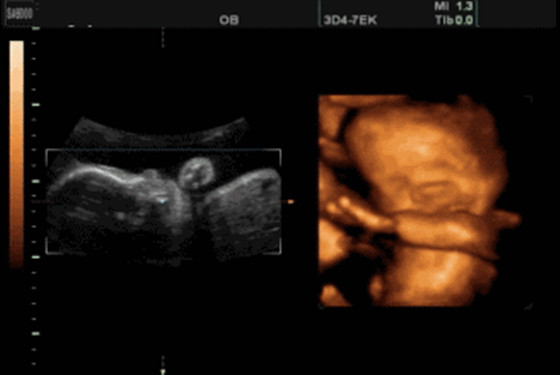

事实上,通过四维彩超是可以很直观立体的查看胎儿器官的,与普通B超相比四维彩超有更高的分辨率,对于胎儿的外生殖器官的辨认会更准确无误,很容易从彩超图中看出区别的。只不过,医院有规定医生即便是知道,也不会直接泄露胎儿的性别。熟一点的医生也只是间接性的提示一下,并不敢直接的告诉你怀的是男孩还是女孩的。这里想要强调的是为了避免误差,建议在怀孕24-28周时做胎儿肢体及脏器方面的检查,虽然怀孕16周时也可以看出胎儿性别,但是它并不是最佳的时机。

@YUHI221:四维彩超肯定能清楚的看出孩子的生殖器,只是医生不说罢了。我一个做医生的朋友透露过,女孩的生殖器图片为三条线,而男孩的生殖器图片好像蘑菇一样是凸起来的。